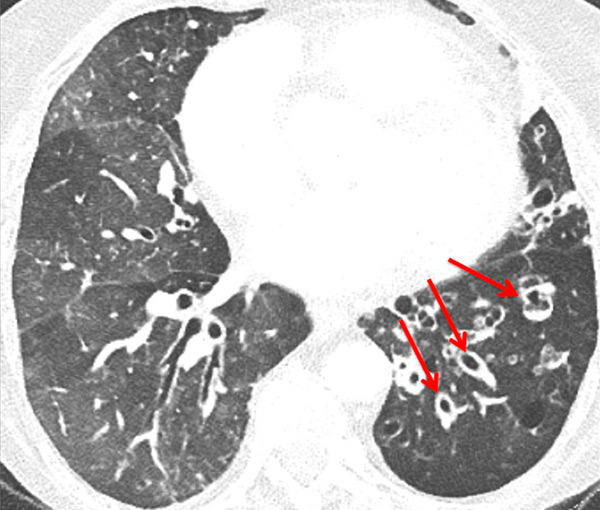

Figure 6

Perfusion heterogeneities in idiopathic pulmonary artery hypertension (stars) in two different patients (A/B). The dilatation of the arteries in pulmonary hypertension (arrows) is not always observed depending on the severity of pulmonary hypertension.